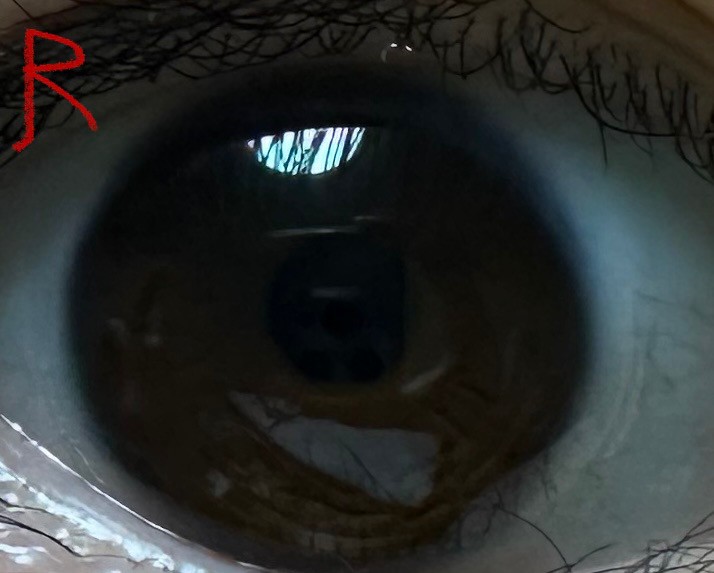

콘택트 렌즈 착용 시 테두리가 눈에 띄게 보이고 건조한데 왜 이럴까요?

이 렌즈가 이 전에도 한 3-4달 정도 사용해본 렌즈인데 이번에 새로 산 후에 밑에 사진 첨부했듯이 왼쪽 눈만 착용했을 때 렌즈 테두리가 눈에 띄게 보이고 비교적 엄청 건조합니다ㅜ 거의 한 시간마다 인공 눈물을 넣어줘야 될 정도예요...

제가 왼쪽 눈이랑 오른쪽 눈 도수가 달라서 두 개를 따로 샀는데 왼쪽 눈만 계속 이러니까 렌즈가 불량인가 싶기도 하네요...

• 1번 째 사진

• 2번 째 사진